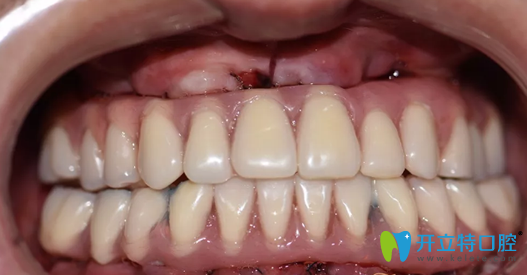

重慶牙博士口腔種植牙術(shù)前照片:

重慶牙博士口腔種植牙術(shù)前照片

這一口牙真的讓人不忍直視,說實話,初看上去真的有點適應(yīng)不良呀,牙周病如此嚴(yán)重,想必莫先生應(yīng)該被牙痛折磨的不清吧。

種植牙術(shù)后即刻照片及修復(fù)后CBCT影像:

重慶牙博士徐孟輝種植牙術(shù)后即刻照片及修復(fù)后CBCT影像

種植完即刻牙齒情況照片:

徐孟輝種植完即刻牙齒情況照片

哇塞,這樣的牙齒是不是看上去順眼了很多,如果沒有人說的話,你能看出莫先生的牙是后天種植上去的嗎?